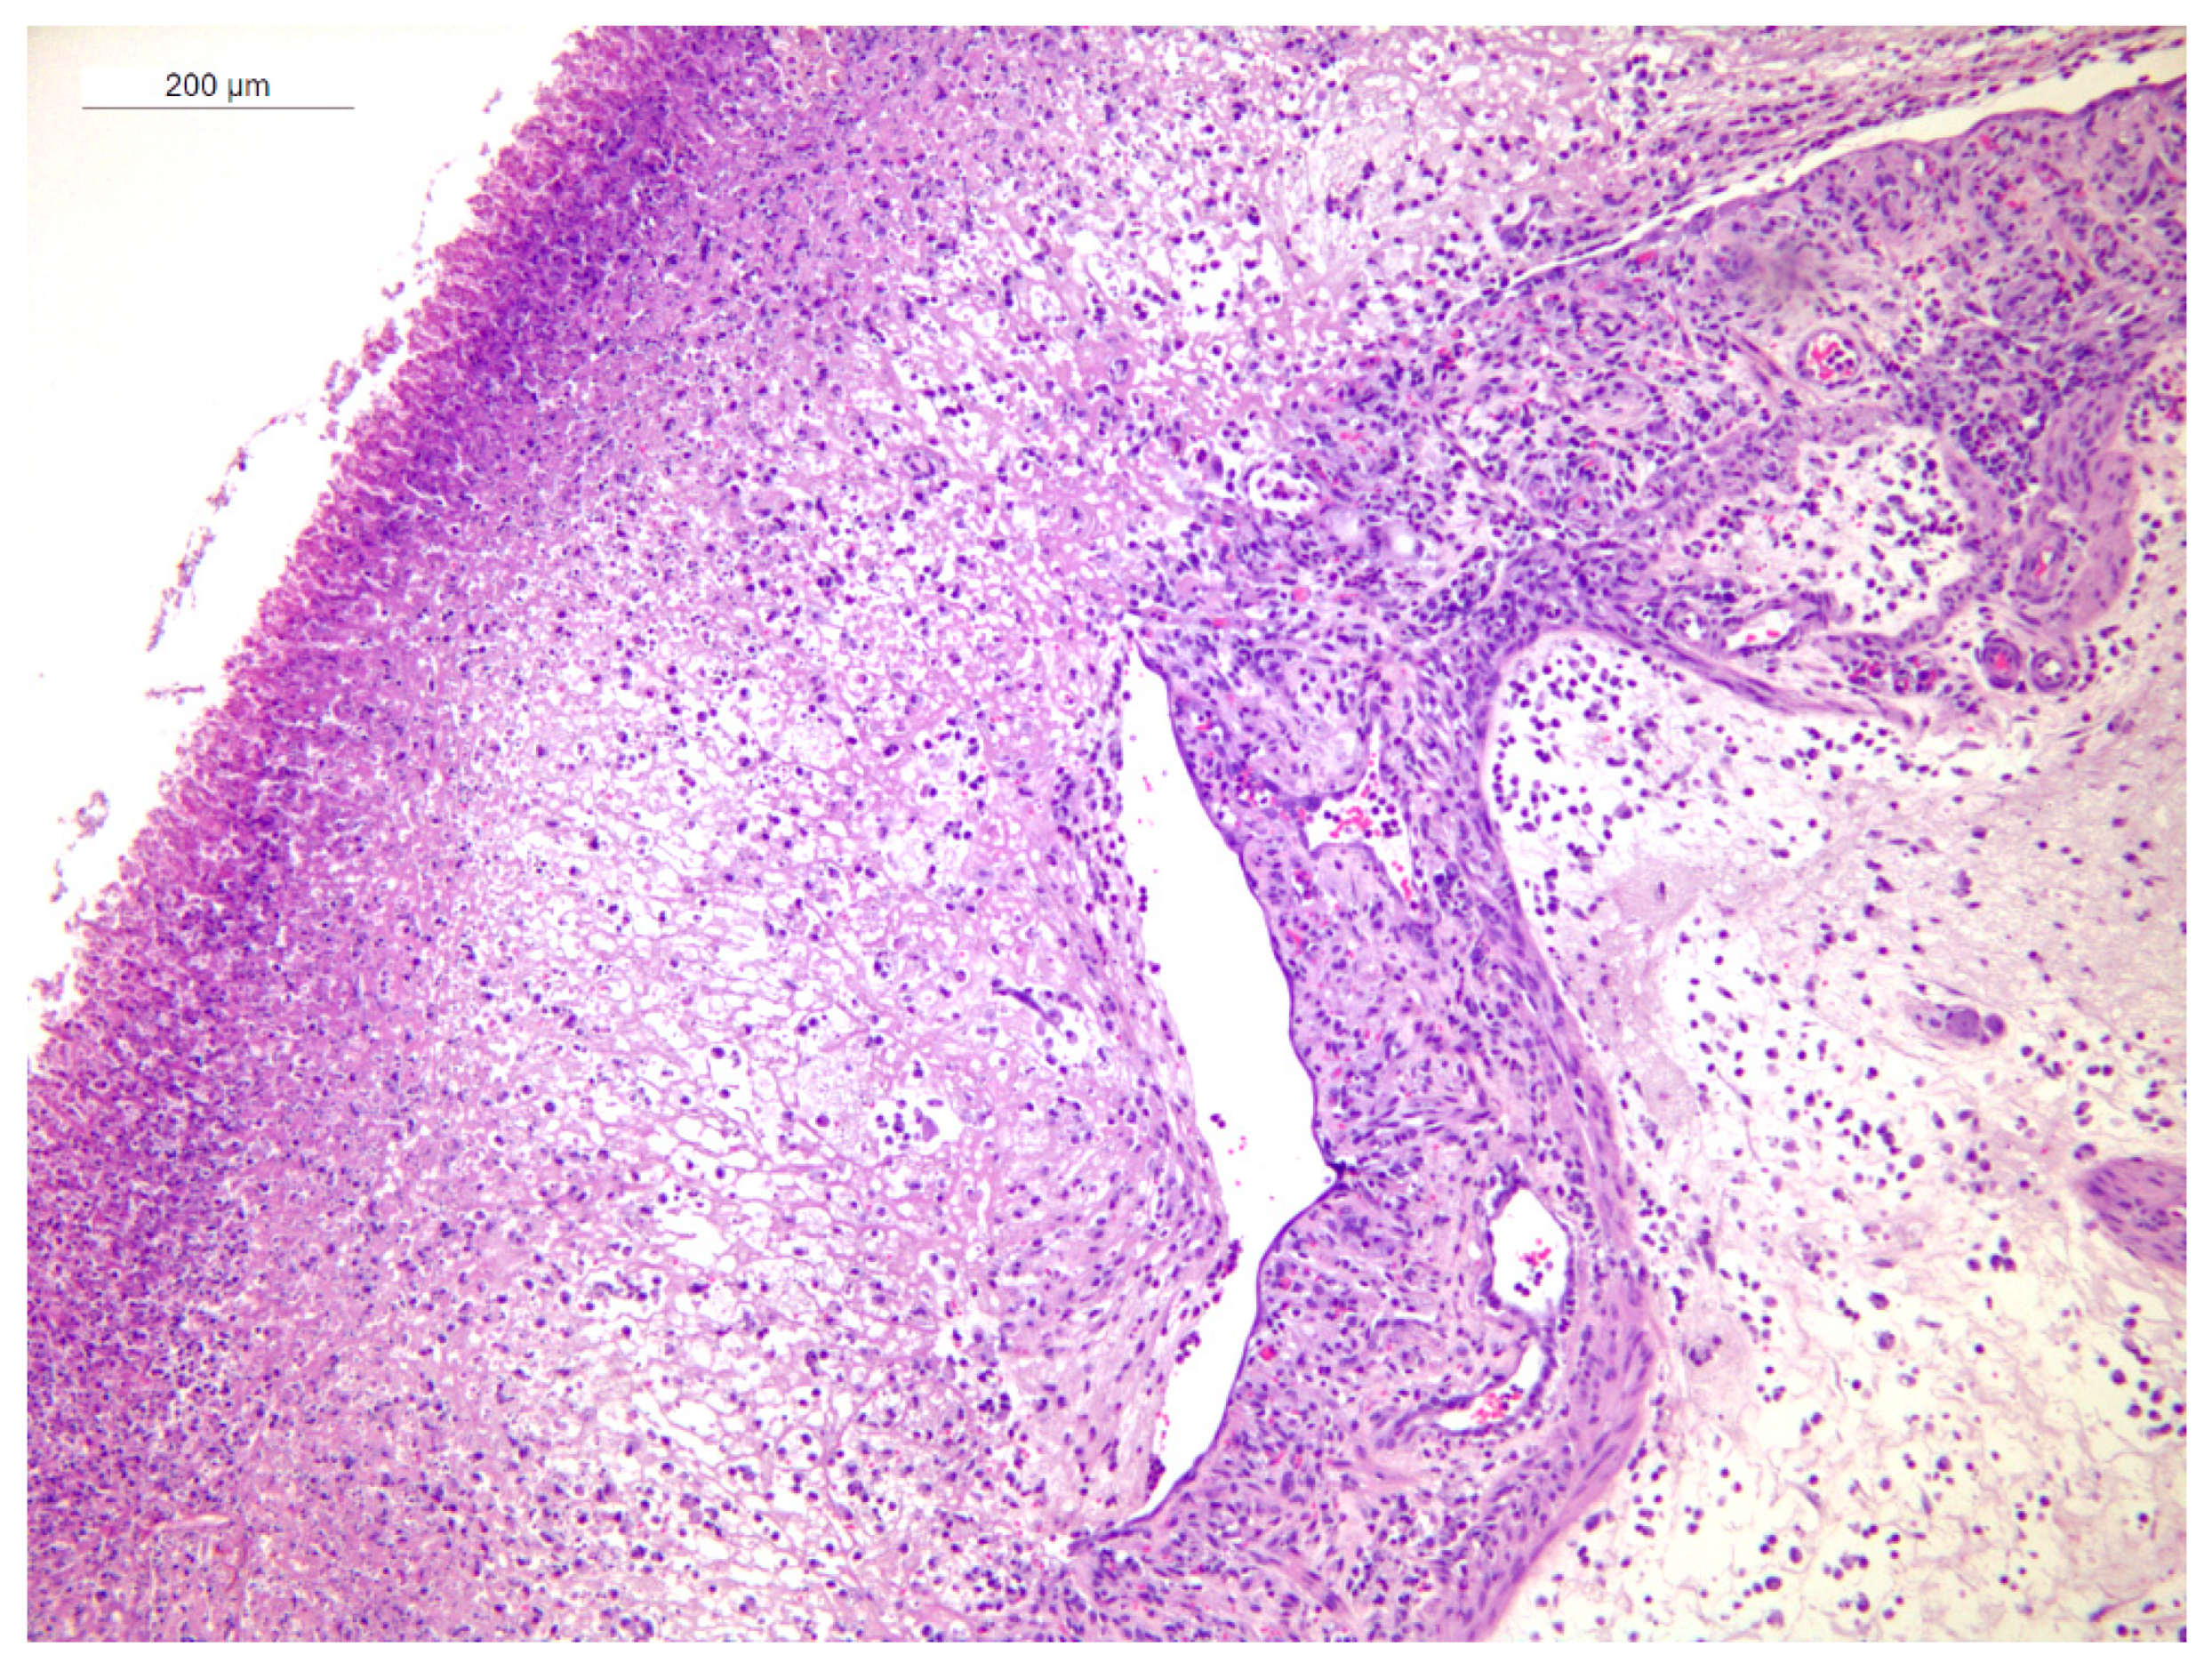

3.4. Histopathology